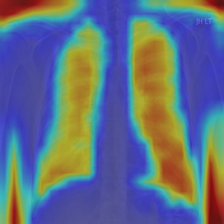

4.7.2 Activation Response Maps

As shown in Fig. 9, given the text lungs, we can find that the activation maps can accurately highlight the target regions. Therefore, we can achieve a higher performance on the downstream tasks. However, the activation maps are imperfect, as the background regions are also highlighted.